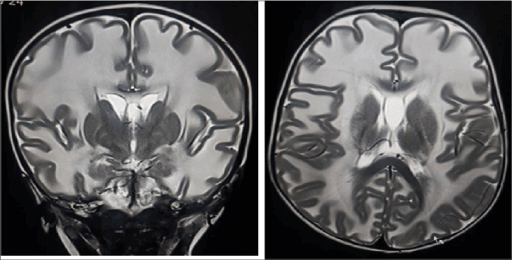

A 18 month old boy born from consanguineous marriage in a muslim family, presented to our department for MRI brain with history of delayed development milestones, especially motor and social. He was born out of normal delivery with uneventful birth history. No history of abnormal body movements and prolonged fever. Abnormally large head is noticed by parents 5 months after birth, which was normal at birth as per parents. On examination, the child has macrocephaly with a HC of 54 cm, (>95th percentile). Rest of physical and systemic examination was normal. MRI brain revealed extensive diffuse homogenous dysmyelination involving the subcortical and deep white matter of the cerebral hemispheres with sparing of basal ganglia and frontal white matter region, consistent with MLC (Figures 3 and 4).

Figure 3. T2 weighted coronal and axial MR shows bilateral symmetrical white matter hyperintensity suggestive of dysmyelination